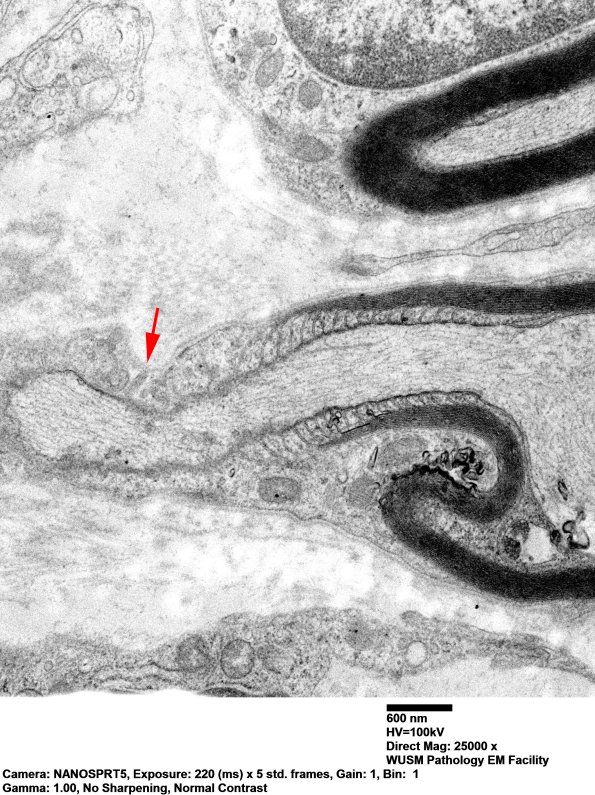

An image of the paranode and node with foci of microvilli (arrow). (electron micrograph)